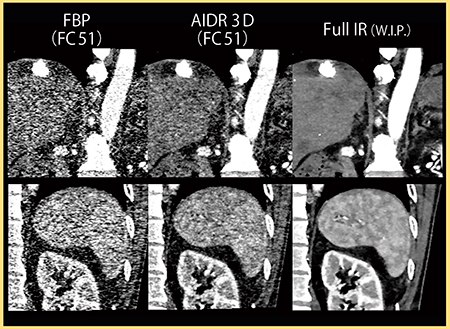

2.肝臓

図5は,80kV,135mAs,1.1mSvで撮影した肝実質の画像である。肝細胞がんが多発しており,淡い低吸収の結節が見られる。AIDR 3Dではノイズに埋もれてわかりにくい腫瘍も,Full IRでは明瞭に視認でき(→),小さな石灰化やリピオドール(◀)もはっきりと描出されている。

図6は同一症例の冠状断像であるが,Full IRでは椎体や上行大動脈周囲のノイズがほぼ除去されている。また,早期動脈相で見られるような,脾臓のまだらな濃染もはっきりと確認できる。

肝実質と筋肉にROIを設定し,軟部組織におけるノイズ低減率を測定したところ,AIDR 3Dでは33〜55%のノイズ低減率であったが,Full IRでは78〜84%であり,大幅な画質改善が期待できる。

図5 肝実質(1.1mSv)

80kV,135mAs,0.5mm

図6 図5の冠状断像